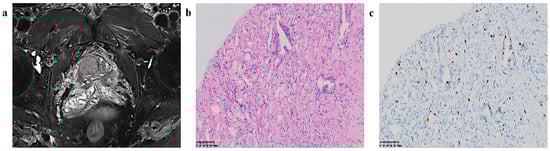

2.4. Radiomics Feature Extraction

Figure 2. Region of interest (ROI) segmentation and corresponding pathological pictures. (a) ROI segmentation, (b) Loupe image of hematoxylin–eosin stain shows the GS = 4 + 3 (×20), (c) Loupe image of immunohistochemical stain shows the percentage.